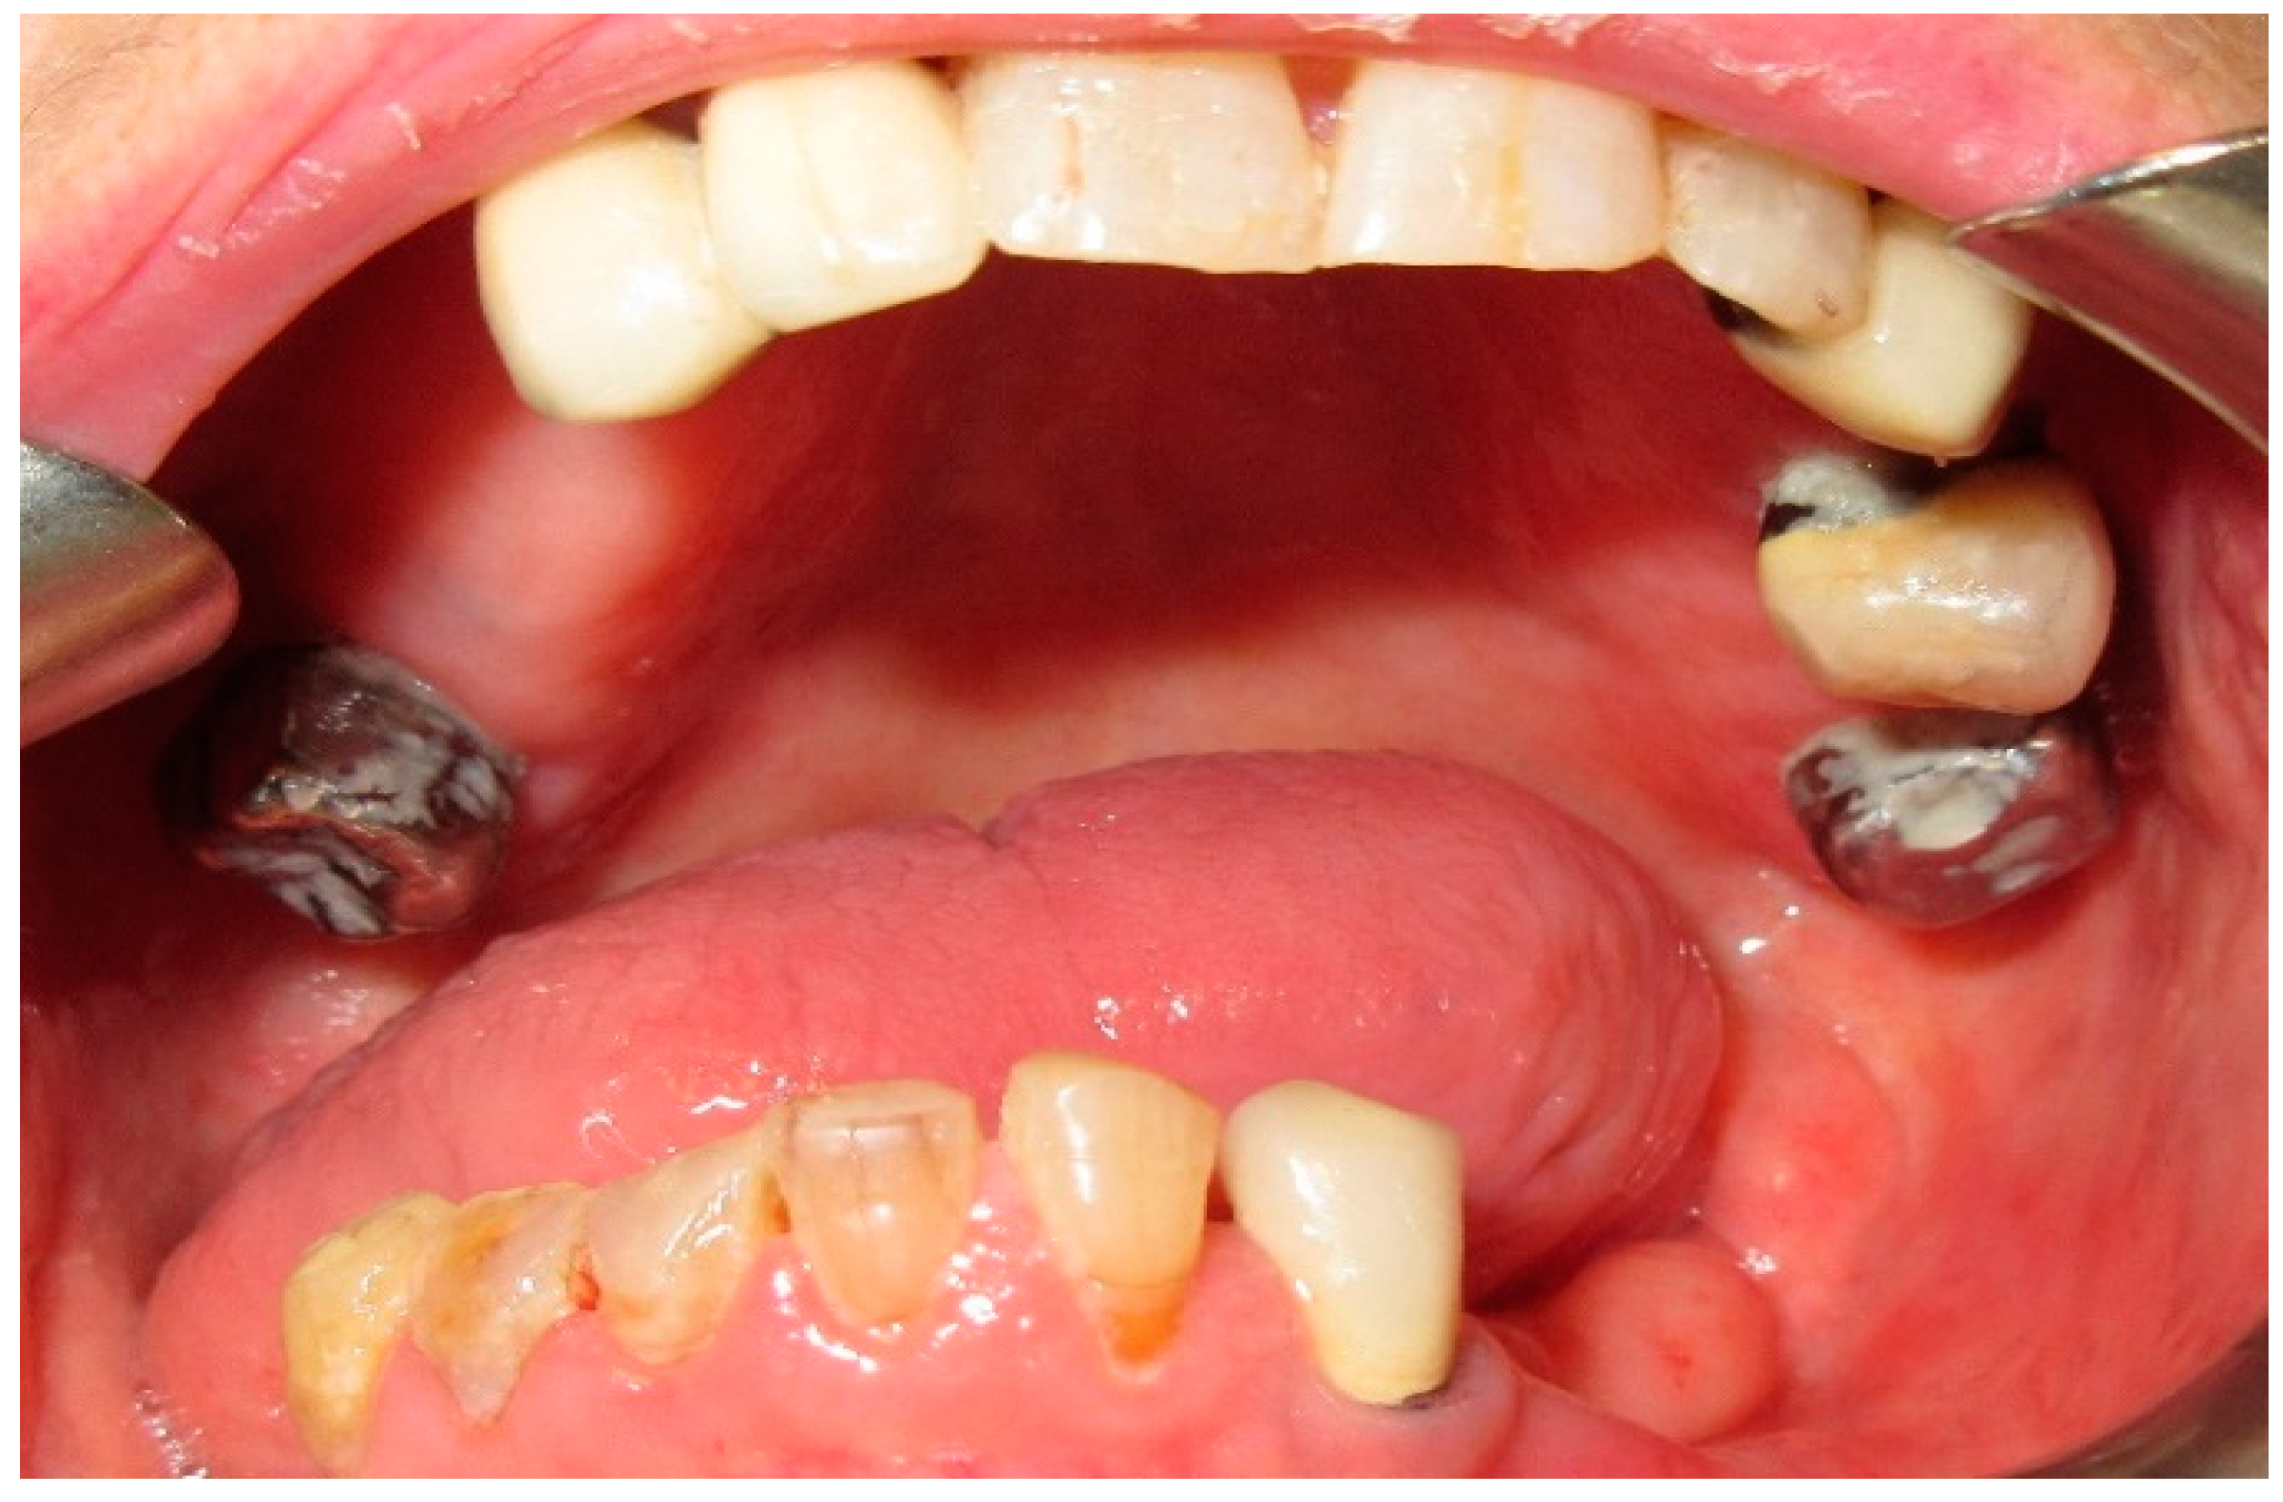

The patient of case 5 displayed a moderate latero-deviation following an L2-3 hemimandibulectomy with partial resection of the coronoid process (Figure 21 and Figure 22). Photos of interocclusal contact between the upper and lower teeth were not feasible due to the patient being unable to successfully close her mouth with the dental gag inserted.

The patient’s surviving teeth (32, 33, 34, 35) are not sufficient to stabilize and counteract the deviation towards the affected side, which not only develops on the transverse plane (left to right) but also on the frontal plane (back to front).

Figure 21. Patient with hemimandibulectomy L,2,3 in extra- (a,b) intraoral view.